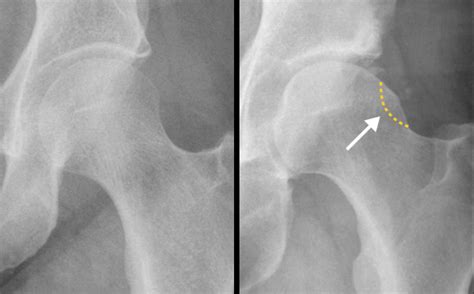

In patients with Cam Impingement, the shape of the femoral head is not perfectly round. Instead, it has an abnormal bony growth, often referred to as a "cam" lesion. Because this bone is irregular, it cannot rotate smoothly within the socket. As you move, especially during hip flexion or internal rotation, this extra bone bumps into the rim of the socket, pinching the labrum and causing damage to the articular cartilage.

• X-rays: Standard views help the doctor visualize the shape of the femur and the degree of the bony prominence.

• MRI or MRA: These scans are critical for evaluating the soft tissues, specifically looking for labral tears or cartilage thinning that might have resulted from the impingement.